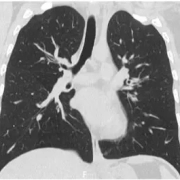

Dupilumab effective for refractory asthma complicated by recurring chronic eosinophilic pneumonia

Dupilumab promising treatment for refractory asthma complicated by recurring chronic eosinophilic pneumonia suggests a new study published in the Nagoya Journal of Medical Science.

Dupilumab-induced hypereosinophilia is mediated by blockade of the IL-4/IL-13 pathway, which reduces eosinophil migration from peripheral blood. The increase in peripheral blood eosinophils may lead to chronic eosinophilic pneumonia (CEP) and/or eosinophilic granulomatosis with polyangiitis, but a direct causal connection between dupilumab and eosinophilic lung diseases has not been established.

A 33-year-old Japanese woman with bronchial asthma since age three was treated with fluticasone propionate plus salmeterol twice daily after several asthma exacerbations at age 17. Her course was complicated by chronic eosinophilic pneumonia at age 33 which resolved without the need for systemic steroids. However, in the four months following resolution of her chronic eosinophilic pneumonia, the patient had three asthma exacerbations, and a recurrence of chronic eosinophilic pneumonia, with blood leukocytes of 8500/µL, of which 25.0% were eosinophils. She was treated with prednisolone 50 mg/day, but she could not continue this dose due to the onset of myalgia. Then she had relapsing chronic eosinophilic pneumonia twice within three months. She was treated with prednisolone 15 mg/day for chronic eosinophilic pneumonia, but she had persistent asthma for more than one month; dupilumab was added at 600 mg, followed by 300 mg every two weeks. In the first month of treatment with dupilumab, the patient’s asthma symptoms resolved completely, and she had only one relapse of chronic eosinophilic pneumonia. In 12 months of follow-up, she had neither an asthma exacerbation nor another relapse of chronic eosinophilic pneumonia. Dupilumab may be a promising treatment for patients with refractory asthma complicated by recurring chronic eosinophilic pneumonia and undesirable steroid side effects.